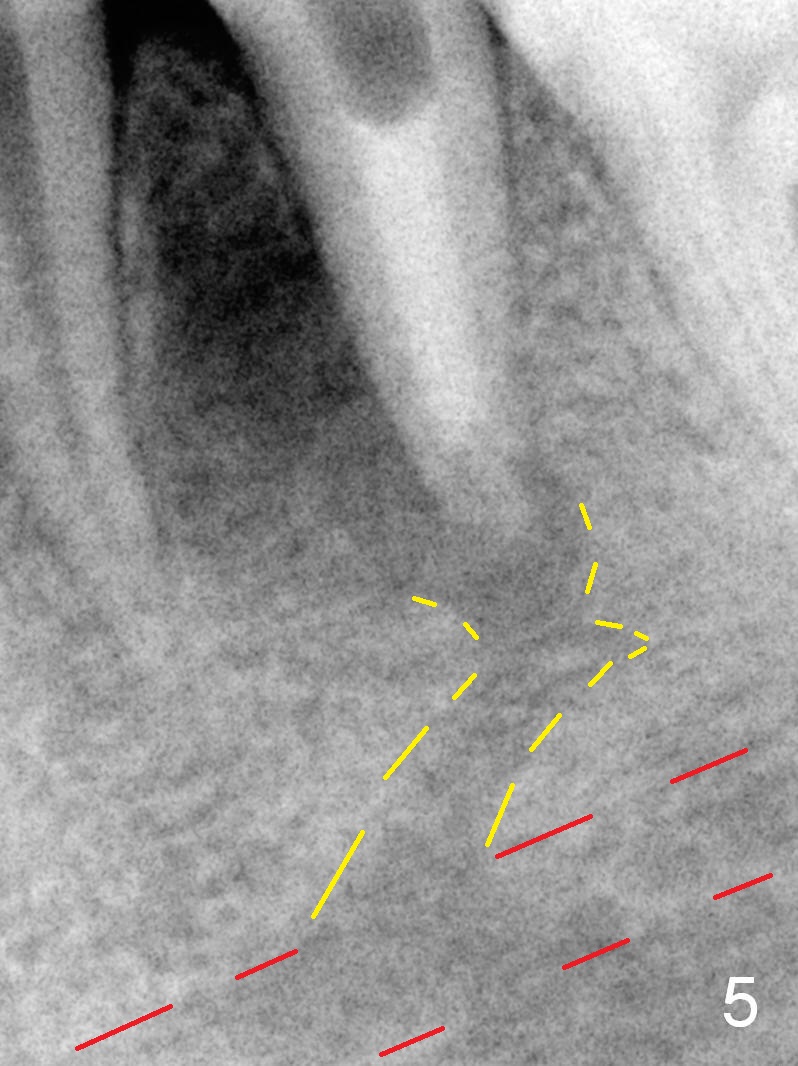

A 13-year-old girl has a buccal apical fistula at the tooth #20 with large periradicular radiolucency (Fig.1 *). After canal debridement, calcium hydroxide paste is placed in the canal (Fig.2 *). One month later, the fistula does not disappear with light percussion. New paste is placed (Fig.3). Two months later, the fistula disappears without percussion. The existing paste (Fig.4) is changed (Fig.5 (yellow: radiolucency; red: Inferior Alveolar Canal)). Another 2 months later, the fistula does not recur; as before, the paste density decreases, so does periradicular radiolucency (Fig.6). Root canal is packed (Fig.7). Six months postop, periradicular radiolucency continues to decrease, while the lamina dura at the apex is discontinuous (Fig.8 between arrowheads). Seven years postop, the lamina dura at the apex is seemingly intact (Fig.9). The patient remains asymptomatic at #20. In fact there is an acute infection at #29.